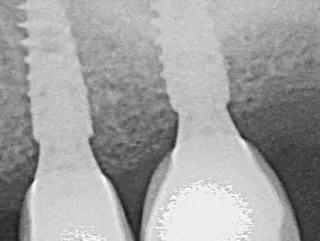

Dr Jean-Baptiste VERDINO The new design of the Axiom X3® implant presents several surgical advantages, such as: Simplified drilling procedure... Read more

Dr Pierre BRUET The case demonstrated the capacity of Axiom X3® to achieve good stability in bone tissue without damaging it... Read more